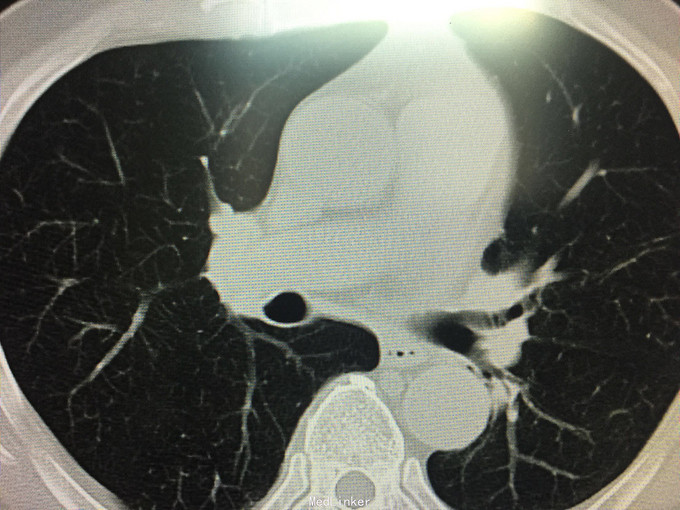

男性,70岁, 主诉:发现左肺上叶占位12个月 现病史:2014.10月患者出现胸背部疼痛不适,对症理疗未见好转。2014.11月出现咳嗽,咳痰带血丝,行胸部CT检查示:左肺上叶占位病变,恶性可能性大。2014.11.13患者行PET/CT检查提示:左肺上叶软组织密度肿块影伴周围片状密度增高影,代谢增高,考虑恶性病变伴周围炎性改变。纵隔内及左肺门多发淋巴结影,代谢增高,考虑为恶性病变转移。左肾上腺结节,代谢增高,考虑为恶性病变转移。第2胸椎棘突骨质破坏,代谢增高,考虑为恶性病变转移。肿瘤标志物:CA125 625 U/ml。因肿块位置较高,未行纤维支气管镜取病理,患者因年龄大,拒绝行肺肿物穿刺活检,故病理不明确。但根据肿瘤影像学形态及理化检测,怀疑为腺癌,建议患者行TKI靶向治疗,同时给予双磷酸盐治疗骨转移。患者口服TKI一个月后复查胸部CT肿块明显缩小,胸背部疼痛消失。患者现口服TKI约11个月,无明显咳嗽咳痰,无背部疼痛。近1周,患者诉偶尔咯鲜红色粘痰,伴有咽部及胸前区闷痛疼痛无明显咳嗽症状,为求复查而来诊。复查胸部CT较之前对比未见明显变化。复查肿瘤标志物:CEA、CA-125、NSE均未见异常。

查体:BP 165/75mmHg,双肺呼吸引清,未闻及干湿罗音,心音钝,心律齐,心率72次/分,各听诊区未闻及杂音。腹平,未见胃肠型及蠕动波,腹软,全腹无压痛,无反跳痛及肌紧张,肝脾肋下未触及,墨菲氏征(-),移动性肝肾区无叩痛,移动性浊音(-),肠鸣音4次/分。 辅助检查:肝胆脾彩超:未见明显异常。 胸部CT:较2015.8月对比未见异常,左肺上叶陈旧性改变。 肿瘤系列:CEA、CA-125、NSE均未见异常。